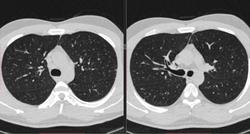

По jpeg впечатление очаговых изменений верхних долей и умеренного увеличения лимфоузлов средостения. Туберкулез на первое место.

Моё мнение то же самое, туберкулез. Добавила изображения.

Посев мокроты на туберкулез отрицательный. Пульмонолог по КТ ставит саркоидоз легких 2 степени. Какое Ваше мнение?

В диф. ряд на первое место предполагаю все же саркоидоз легких и ВГЛУ (по одной из классификаций 2 стадия, а не степень). В плане дальнейшего диагностического алгоритма: